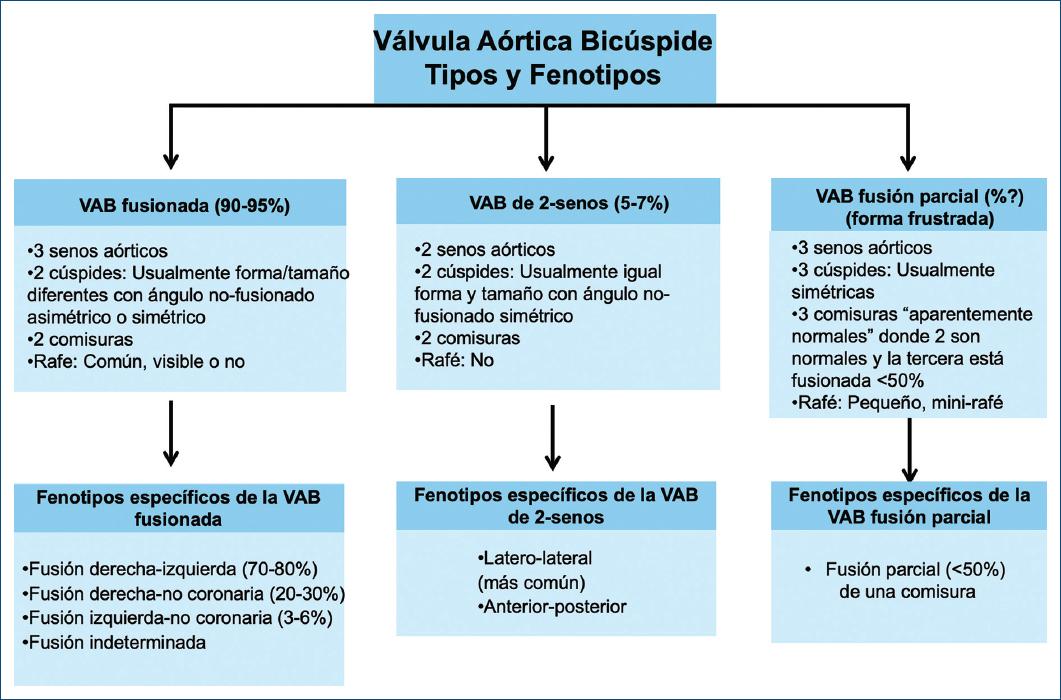

Hay tres tipos de VAB: la VAB fusionada, la VAB de dos senos y la VAB de fusión parcial, cada uno con fenotipos específicos1,6 (Fig. 4).

Figura 4 Tipos y fenotipos específicos de la válvula aórtica bicúspide (VAB) congénita. Hay tres tipos principales de válvulas aórticas bicúspides (VAB) y cada tipo tiene fenotipos específicos: VAB fusionada (fusión de cúspide derecha-izquierda, fusión derecha-no coronaria, fusión izquierda-no coronaria y fenotipos indeterminados); VAB de dos senos (fenotipos latero-lateral y antero-posterior) y VAB de fusión parcial o VAB forme fruste (forma frustrada) (rafé pequeño, fenotipo único). Simétrico o asimétrico se refiere al ángulo de las comisuras de la cúspide no fusionada (Fig. 9).

VÁLVULA AÓRTICA BICÚSPIDE FUSIONADA

La VAB fusionada es la más común (Figs. 5 y 6) y representa aproximadamente el 90-95% de los casos de VAB2,28. La VAB fusionada se caracteriza por dos de las tres cúspides apareciendo fusionadas o unidas dentro de tres senos aórticos distinguibles, lo que resulta en dos cúspides funcionales (una fusionada o unida y la otra no fusionada) que generalmente son diferentes en tamaño y forma (Figs. 6-8), con ángulos comisurales de la cúspide no fusionado de diversos grados (Fig. 9). Comúnmente, los pacientes con una VAB fusionada demuestran una dominancia excéntrica del seno aórtico no fusionado y su cúspide (en comparación con los otros dos senos y dos cúspides fusionados), independientemente de la edad35 (Figs. 6 y 7). Con frecuencia (aproximadamente el 70%), pero no siempre (Fig. 8), se observa una cresta fibrosa congénita entre las cúspides fusionadas, denominada «rafé»28,36. La presencia de un rafé se ha asociado con la progresión de la disfunción valvular (particularmente estenosis aórtica) y la futura cirugía valvular26,36,37. Un rafé puede estar presente pero no ser visible inicialmente en el ecocardiograma y puede hacerse visible años después38.

Hay tres fenotipos específicos de VAB dentro del tipo fusionado: fusión de cúspide derecha-izquierda, fusión de cúspide derecha-no coronariana y fusión de cúspide izquierda-no coronariana (Figs. 4, 6 y 7). El fenotipo de fusión derecha-izquierda es el más común (70-80%)2,28,39. El fenotipo de fusión derecha-izquierda es también el acompañante más común de todas las variaciones de fenotipos aórticos (aorta normal, aorta ascendente dilatada, raíz dilatada, arco dilatado) y de la disfunción valvular (insuficiencia o estenosis). Aunque este fenotipo de fusión derecha-izquierda desarrolla estadísticamente más estenosis aórtica2, se ha asociado en algunos pacientes40,41 con dilatación de la raíz aórtica, insuficiencia aórtica y preponderancia masculina (estas asociaciones se han denominado el «fenotipo de raíz»)38,39. La fusión derecha-izquierda también está fuertemente asociada con coartación aórtica en niños42.

El fenotipo de fusión derecha-no coronariana es el siguiente más común (20-30%). Se asocia con una mayor prevalencia de estenosis aórtica en adultos37 y también predice de forma independiente la progresión de la insuficiencia aórtica en adultos33. Del mismo modo, el fenotipo de fusión derecha-no coronariana se asocia con una progresión más rápida de la estenosis aórtica y la insuficiencia en niños y adolescentes42,43. El fenotipo de fusión izquierda-no coronariana es el fenotipo menos común (3-6%) en todos los estudios.

Es apropiado referirse a los fenotipos fusionados como VAB con fusión derecha-izquierda, fusión derecha-no coronariana o fusión izquierda-no coronariana. Ocasionalmente, es posible reconocer una VAB fusionada pero no poder discernir el fenotipo de fusión, en cuyo caso el término VAB con fusión indeterminada es apropiado (Fig. 4). Es importante reconocer que algunas VAB fusionadas pueden no tener un rafé congénito28 o puede tener un rafé que no es visible por medio de imágenes38, sin embargo tienen tres senos aórticos distinguibles y generalmente se pueden identificar las dos cúspides fusionadas (Fig. 8).

VÁLVULA AÓRTICA BICÚSPIDE DE DOS SENOS

La VAB de tipo dos senos es poco común, representando aproximadamente el 5-7% de los casos de VAB2,6,28. En contraste con el tipo fusionado, la apariencia de la VAB de dos senos no sugiere que dos de las tres cúspides se hayan fusionado, sino que hay dos cúspides de aproximadamente el mismo tamaño y forma, que cada una ocupa 180° de la circunferencia anular, y que estas se «formaron» dentro de dos senos aórticos solamente, lo que resultó en una válvula de dos senos/dos cúspides (Figs. 11 y 12) con ángulos comisurales de 180°. Es difícil determinar cuáles dos cúspides podrían haberse unido para formar una VAB de dos senos, pero generalmente es evidente si las cúspides son latero-laterales (de lado a lado) o antero-posteriores (adelante y atrás) dentro del plano de la base del corazón de eje corto (Figs. 11 y 12); por lo tanto, estos son los dos fenotipos específicos de la categoría de la VAB de dos senos. La VAB latero-lateral de dos senos tiene una arteria coronaria que surge de cada seno, mientras que la VAB antero-posterior puede tener una arteria coronaria que surge de cada seno o ambas arterias coronarias que surgen del seno anterior (Figs. 11 y 12). La VAB de dos senos probablemente representa una expresión más grave de los mecanismos embriológicos que conducen a la VAB fusionada. Es apropiado referirse a estos fenotipos como VAB latero-lateral de dos senos y VAB antero-posterior de dos senos. Ocasionalmente, a pesar de la sospecha, puede ser difícil estar seguro de si solo hay dos senos, en cuyo caso se pueden usar términos como posible o probable VAB de dos senos. Hay una falta de datos científicos sobre las asociaciones clínicas/pronósticas de la VAB de dos senos, que representa una forma «morfológicamente severa» de la VAB. Por lo tanto, esperamos que por medio de este sistema de nomenclatura/clasificación, la comunidad investigadora dirija más atención hacia este tipo de VAB.

LA VÁLVULA AÓRTICA BICÚSPIDE DE TIPO FUSIÓN PARCIAL (O FORME FRUSTE)

Se desconoce la prevalencia de este tipo de VAB de fusión parcial recientemente descrito (o VAB forme fruste [forma frustrada])45 (Fig. 13). La apariencia de la VAB de fusión parcial es la de una válvula aórtica tricúspide típica con tres cúspides simétricas con una apertura triangular sistólica y ángulos comisurales de 120°, sin embargo en la inspección quirúrgica o la imagen de alta resolución se observa menos del 50% de fusión entre dos cúspides en la base de una comisura, formando un pequeño «minirafé»6,45-47. Es importante reconocer y seguir estudiando la VAB de fusión parcial, que se ha descrito con mayor frecuencia en el quirófano en pacientes sometidos a cirugía por dilatación aórtica45 (Fig. 14)47. Esta VAB forme fruste resulta en la alteración de los patrones de flujo aórtico, que consiste en un aumento de la excentricidad del flujo y un aumento de los vórtices46, quizás explicando parcialmente la aparente alta prevalencia de dilatación aórtica en estos pacientes. Referirse a este fenotipo como VAB de fusión parcial o VAB forme fruste es apropiado, al igual que señalar entre qué cúspides se produce la fusión: derecha-izquierda, derecha-no coronariana y así sucesivamente.